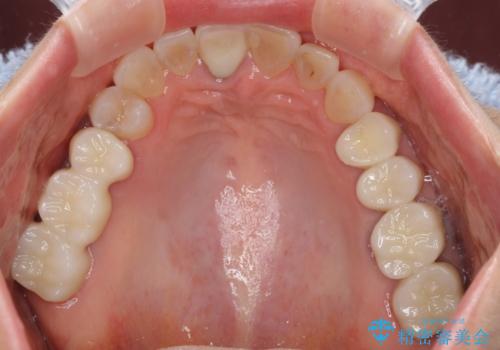

金属を全てセラミックに メタルフリー治療

- 口腔内にある銀歯を全て外したいとのことで来院された患者様です。

土台に含まれている金属も含め、口腔内の金属は全て除去し、抜歯しなければならない歯は抜歯し、オールセラミッククラウンやセラミックインレーにて治療することとしました。

上下奥歯の抜歯を同時期に行わず、下顎の治療を終えてから上顎を抜歯して治療を進めたため、1年ほどの期間を要しました。

口の中を一切気にしなくて良くなり、患者様には大変満足していただきました。